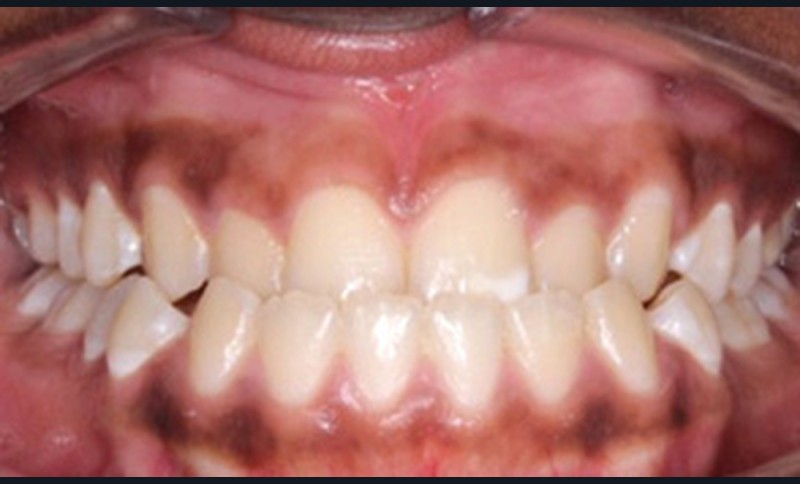

Examen clinique (fig. 1a-h)

À l’examen de face, Anisa présente un visage ovalaire, des hémifaces symétriques, des lignes horizontales parallèles, une augmentation de l’étage inférieur, une occlusion labiale légèrement forcée et des dents mandibulaires exposées au sourire. Les profils général et sous-nasal sont concaves avec un angle naso-labial augmenté et une prochéilie inférieure.

L’examen clinique endo-buccal révèle une denture adulte jeune avec un inversé d’articulé antérieur de 13 à 23, des tatouages gingivaux ethniques et des taches de décalcifications, un parodonte sain mais un brossage insuffisant.

L’arcade maxillaire est en V et la voûte palatine profonde. L’arcade mandibulaire a une forme en U (non-concordance des formes d’arcade) et présente des malpositions des dents cuspidées. La médiane mandibulaire est décalée à gauche de 2 mm ; le recouvrement antérieur est de 2 mm ; les molaires sont en classe III avec un surplomb inversé.